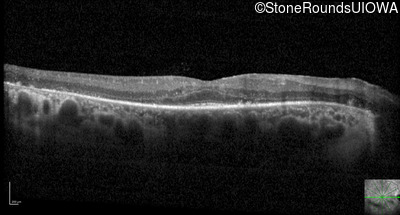

Optical Coherence Tomography - Right - 20/40

Exemplar / OCT Stack

OCT Stack

Optical Coherence Tomography - Left - 20/30